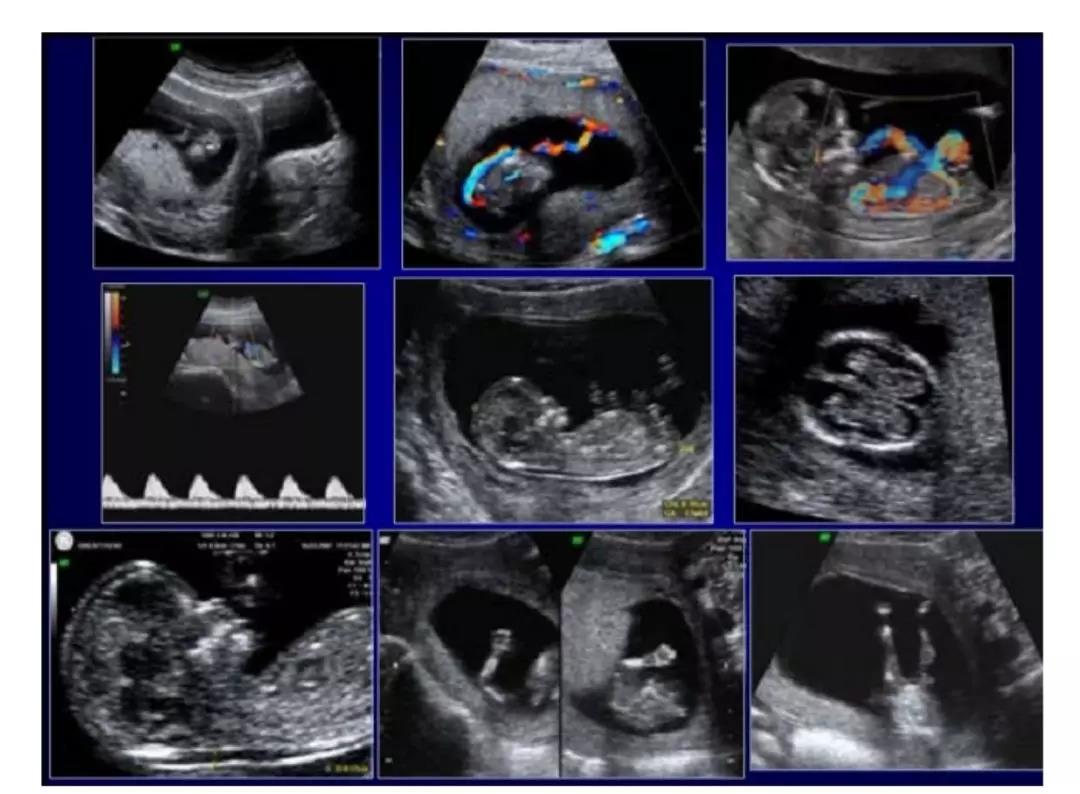

(箭头所指为胎儿颈项透明层厚度)

(图为增厚的NT)

当然,超声进行NT检查时,并非仅仅测量颈项透明层厚度,还需要观察的有胎儿头臀径、胎儿颅脑横切面、胎儿四肢等多个部位,这些对于胎儿早期都具有重要的意义,所以说,NT是每个宝妈都不能忽视的、非常重要的检查。